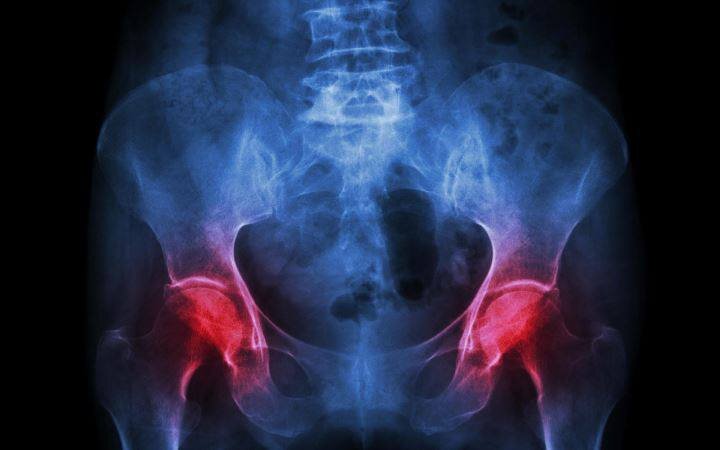

Бедренные кости и поясничный отдел позвоночника 173 участников в рамках исследования были подвержены облучению лёгкими дозами радиации с целью изучения минеральной плотности костей (МПК). МПК достигает пиковых значений в возрасте приблизительно 30 лет, что, по словам ученых, говорит о том, что те, кто в молодости не выполнял упражнения, формирующие прочный скелет, в отдалённой перспективе подвергаются повышенному риску развития остеопороза.